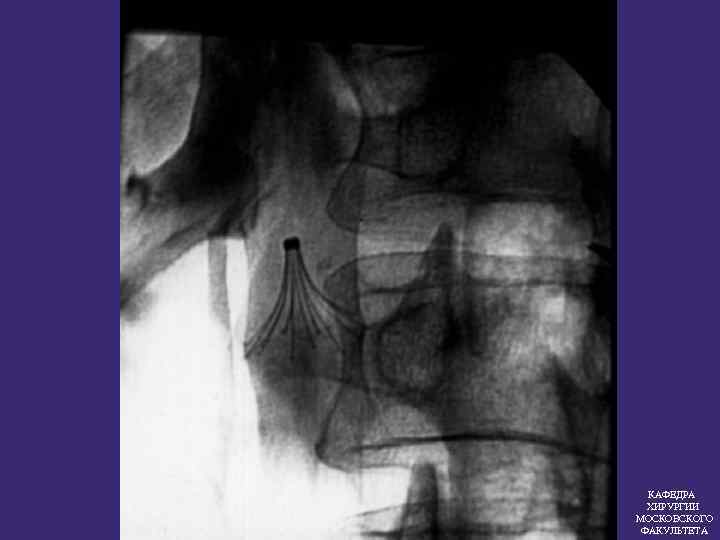

ПРОТИВОЭМБОЛИЧЕСКИЕ КАВАФИЛЬТРЫ Эффективность кава фильтров 97, 5% КАФЕДРА ХИРУРГИИ МОСКОВСКОГО ФАКУЛЬТЕТА

ПОКАЗАНИЯ К ИМПЛАНТАЦИИ КАВА-ФИЛЬТРА 1. Флотирующие тромбы в системе НПВ 2. Массивная ТЭЛА Повторные ТЭЛА без установленного источника 3. КАФЕДРА ХИРУРГИИ МОСКОВСКОГО ФАКУЛЬТЕТА